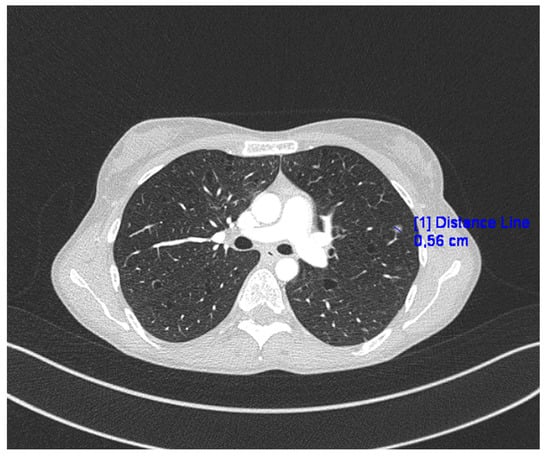

2. Case Presentation